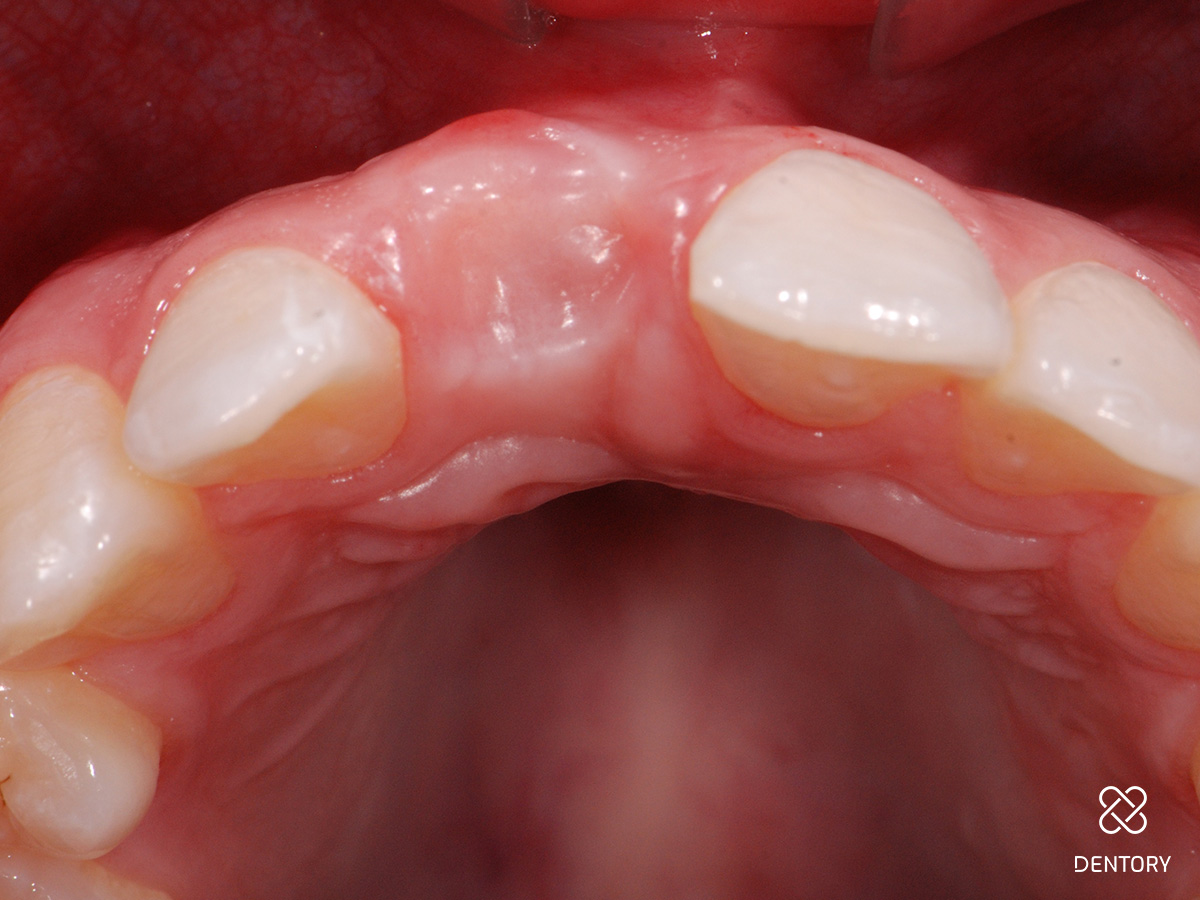

Abbildung 1

Ausgangssituation: Nicht erhaltungswürdiger Zahn 11 aufgrund einer externen Resorption.